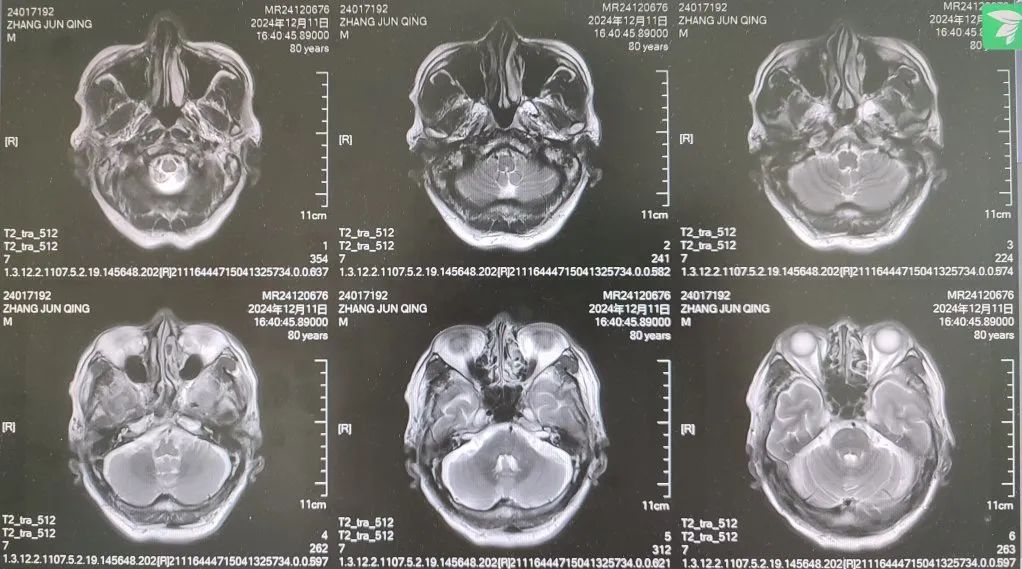

内容提要 很多人都想拥有纤细、健美的双腿,尝试多种健身方法,效果却始终不理想。然而社会上大约有万分之四的人,他们不用减肥,双腿就会慢慢“瘦”下来,如倒置的香槟酒瓶,医学中称之为“鹤腿”。不过这并非自愿,而是源于一种名为“腓骨肌萎缩症”的罕见疾病。近日,市二院神经内二科赵智江主任团队就帮助一位受腓骨肌萎缩症困扰4年之久的患者明确了病因。 #01 “鹤腿”多年不明病因 竟是罕见病作祟 患者80岁,四年前无明显诱因出现步态异常,行走困难,起初以为是劳累所致,并未过多在意。然而,近一年来症状逐渐加重,双下肢膝关节以下麻木、发凉,行走时右下肢有甩脚动作,呈跨阈步态,右足趾背屈不能,同时存在站立不稳、不能蹲下等症状,严重影响日常行走。这一年间,他辗转市内多家医院,经历了无数次的检查和咨询,却始终未能得到确切诊断。 近日,患者经多方打听,来到了以诊治神经疑难病为特色的市二院神经内二科。入院后,赵智江主任为患者进行了细致入微的查体,发现患者双侧大腿下三分之一处及小腿肌肉萎缩。进一步完善头颅、颈椎及胸椎核磁的检查,由于患者存在跨阈步态,结合检查结果,初步考虑为腓总神经麻痹。 头颅、颈椎核磁回报后,基本上排除了神经根的疾病和脊髓疾病。肌电图结果提示四肢周围神经受累,右侧腓总神经损伤更重,修正诊断为周围神经病。然而,周围神经病存在多种病因,需进一步查找病因。赵智江主任结合患者双下肢肌肉萎缩情况,排除其它病因导致的周围神经病,最终明确诊断为腓骨肌萎缩症。 头颅核磁影像 颈椎及腰椎核磁影像 随后,中国医科大学附属第一医院神经内科著名专家何志义教授及辽宁名医、市二院卒中中心主任闵连秋教授在查房时同样肯定了腓骨肌萎缩症的诊断。 腓骨肌萎缩症是一组具有高度临床和遗传异质性的周围神经单基因遗传病,以慢性进行性四肢远端肌无力肌萎缩、末梢型感觉障碍、腱反射减退或消失和高弓足等骨骼畸形为主要临床特征,多为儿童和青少年期起病。该患者老年起病,极为罕见!目前,腓骨肌萎缩症无特效治疗药物,主要以支持治疗为主。今后,患者只要在康复医师的指导下,根据神经损害范围进行合理的康复锻炼,就能保持较好的活动能力,提高生活质量。 市二院神经内二科赵智江主任团队拥有丰富的神经系统疑难疾病诊治能力,曾帮助大量饱受罕见病困扰多年的患者明确了诊断。随着诊疗水平的持续精进,神经内二科将为更多患者提供精确诊断及治疗,为更多的神经疑难疾病明确诊断,为患者带来福音。 #02 人民医院 人民名医 赵智江 主任医师 副教授 ·葫芦岛市第二人民医院神经内二科主任 ·中国卒中学会高级会员 ·中国老年保健医学研究会老年脑血管病分会委员 ·北京神经内科学会脑小血管病学会委员 ·安徽医药杂志审稿专家 专业特色:以脑血管病为核心研究方向,擅长各类神经系统疾病的诊疗,尤其在脑血管病、帕金森综合征、头晕、头痛、癫痫、重症肌无力以及中枢神经系统脱髓鞘等神经系统疑难、危重疾病的诊疗方面积累了丰富的临床经验。主持多项重要科研项目,并将最新的科研成果应用于临床实践,撰写十余篇论文著作。